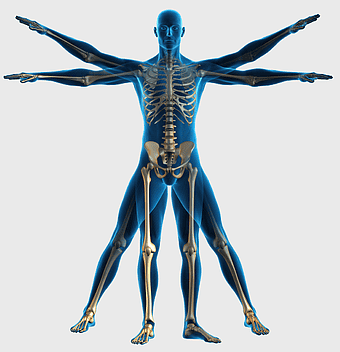

human skeleton, bone structure, nervous system anatomy, joint function, skeletal framework, anatomical illustration, human body composition -